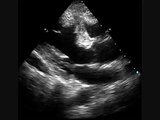

Regional wall motion abnormalities: Echocardiography